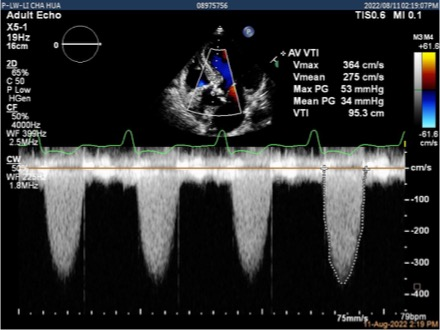

患者,80岁女性,因“反复气紧14年,加重20天”入院。曾于2015年行永久起搏器置入术,合并高血压。STS评分11.878%,虚弱体质。入院超声提示“主动脉瓣中重度狭窄”、“三尖瓣中度反流”。左室舒末径52mm,射血分值35%,主动脉瓣峰值流速3.64m/s,平均压差34mmHg。

行多巴酚丁胺负荷超声后,EF值提升至41.6%,主动脉瓣峰值流速4.48m/s,平均跨瓣压差48mmHg,诊断重度主动脉瓣狭窄。